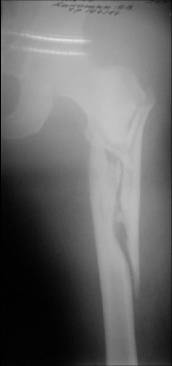

Few days ago I have posted an x-ray of severely comminuted Trochenteric # of Lt. Femur with sub-trochenteric extension of a male patient aged 65 years for opinion of fixation. Eight of you have kindly replied........

I choose Long Gamma Nailing and did it on 24.1.2006.

Now posting the post op x-rays for all of yours comments please. Don't hesitate to criticize me.